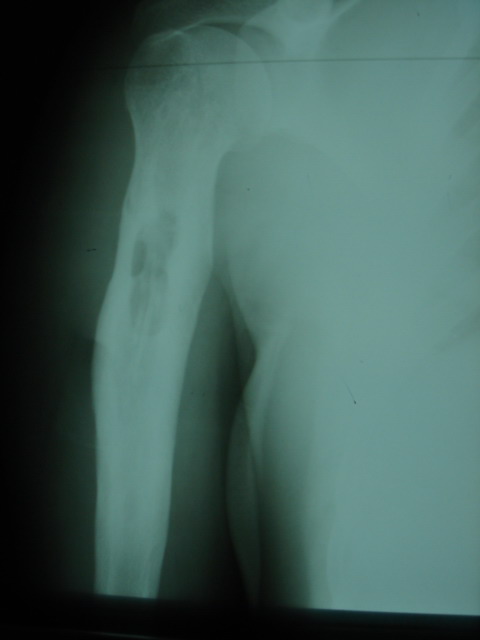

У пациента 31 года после ВКДО голени по Илизарову хронический остеомиелит

дистального отела большеберцовой кости.

Пацент лечится у нас с 2005 года когда по поводу несращения с/3 голени был

применен ВКДО по Илизарову. Достигнута консолидация, аппарат демонтирован.

Через 2 года после сниятия аппарата появился свищ над внутренней лодыжкой.

Осенью 2007 года - ФНЭ, аутопластика дефекта метафиза аутоспонгиозой из

проксимального отдела большеберцовой кости - в течение года ремиссия.

В ноябре-декабре 2008 вновь открылся свищ, произведена хирургическая

обработка, в настоящее время скудное серозное отделяемое. Конечность

полностью опорна, болей нет.